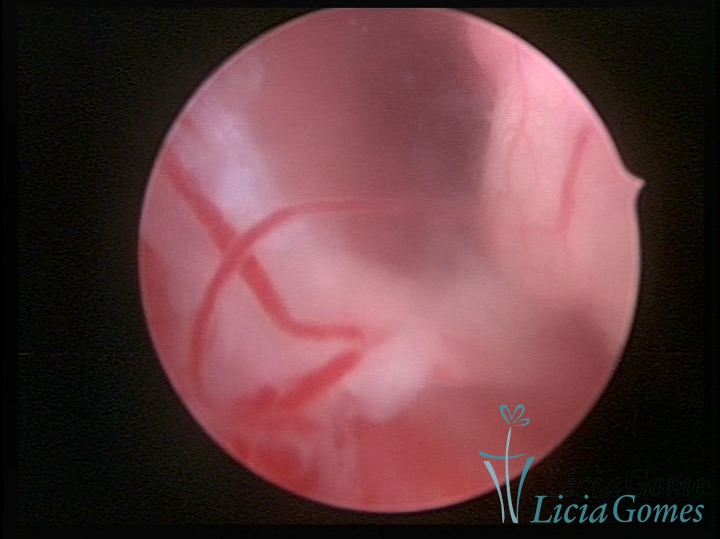

A histeroscopia permite analisar as características da superfície endometrial, não podendo avaliar a profundidade ou o grau de invasão miometrial.

Este pode apresentar uma gama variável de aspectos macroscópicos, com aspecto pseudopolipoide; lembrando tecido cerebroide ou com reação deciduoide;a vascularização superficial é mais evidente e com vasos em formatos de saca-rolha ou espirais visualizando também a vascularização com atípias, com aumento do calibre dos vasos superficiais, pode ser encontrado também tecido em necrose, poderá haver um pequenos dendritos (papilomatoso).